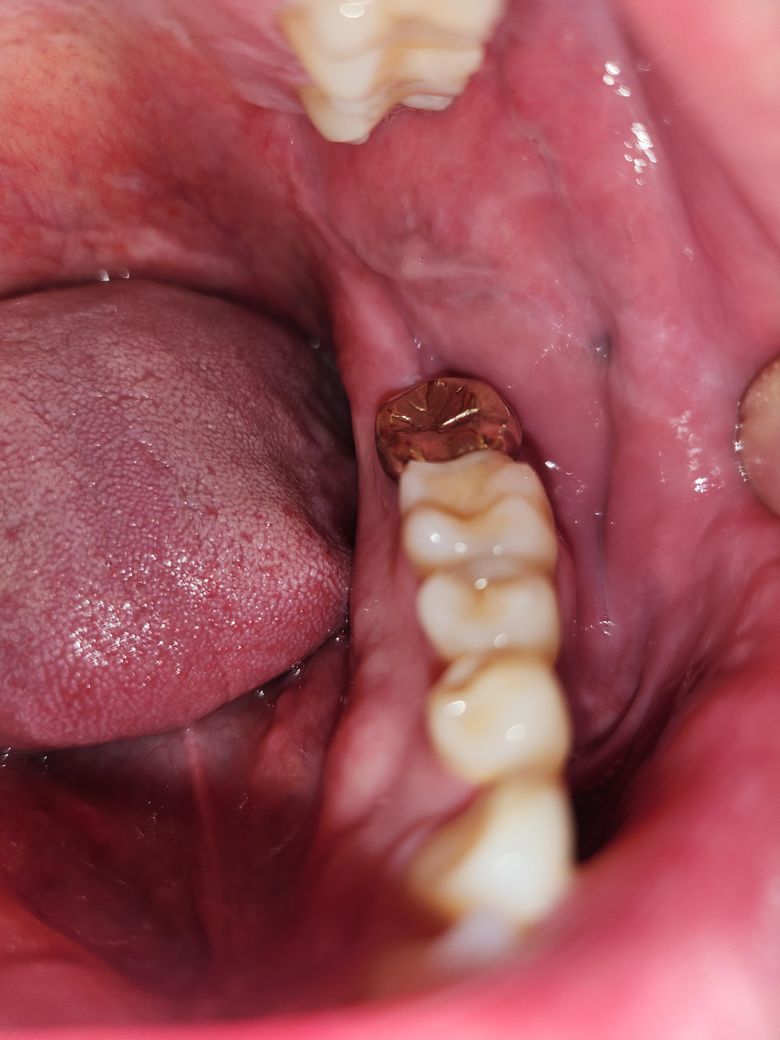

• 2번 째 사진

2.치아와 치아 사이에 볼살이 밀려 들어가 자국이 생긴 것입니다.

3.단순 볼살 맞습니다.